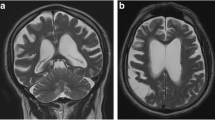

The patient was a 77-year-old right-handed Caucasian man who developed confusion, word-finding difficulty, and slurred speech in early 2020. These symptoms include making phone calls to his wife and asking her non-sensible questions. He lost his words intermittently and forgot names of his family members on several occasions. He recounted old stories as if he were perseverating and answered questions in the affirmative without hearing the question. His mood also became more irritable. His past medical history was notable for a skull fracture after a fall from horseback riding when he was a teenager. As a result, he had undergone a neurocognitive evaluation at age 75 from a memory disorder clinic in a major academic medical center in 2017, and he was diagnosed with a non-specific memory disorder that did not affect his activities of daily living. A non-contrast head CT, obtained in July 2020 after 3 months into his progressive symptoms, showed a hypodense mass in the left temporal lobe of the brain. On the following day, a CT of the torso was unremarkable, but a gadolinium-enhanced head MRI revealed a cystic enhancing mass with central necrosis, measuring 2.5 × 2.4 × 2.7 cm, (Fig. 1A) together with mild cerebral atrophy globally. The mass was associated with extensive T2 and FLAIR (Fig. 1B) signals extending from the inferior left temporal lobe to the insular cortex as well as the internal capsule and the peri-ventricular white matter near the occipital horn on the left side. There was a 6 mm rightward midline shift together with mild effacement of the ambient cistern. The patient underwent a gross total resection of the mass without complication 4 days after obtaining the MRI. Pathology revealed glioblastoma with histological features notable for dense cellularity, moderate to severe atypia and easily identified mitoses. Immunohistochemical staining was negative for the IDH-1 R132H mutation but positive for ATRX, GFAP, Olig-2 and p53. The Ki-67 index showed 20–25% positivity indicating a moderate proliferation rate. Methylation study for the promoter of O6-methylguanine-DNA methyltransferase was not performed. Three weeks after surgery, the patient started involved-field radiotherapy and concomitant daily temozolomide, but only 2 weeks of chemotherapy was administered due to thrombocytopenia, and 6 weeks of radiation treatment was eventually completed 2 months after diagnosis (Fig. 1C and D).

IDH-1 wild-type glioblastoma before and after surgery, radiation, and chemotherapy. MRI from post-gadolinium T1-weighted MP-RAGE (A) and FLAIR (B) sequences demonstrating irregular cystic enhancement and adjacent cerebral edema. The surgical cavity after gross total resection and external beam involved-field radiation as seen on the post-gadolinium T1-weighted MP-RAGE (C) and FLAIR (D) sequences